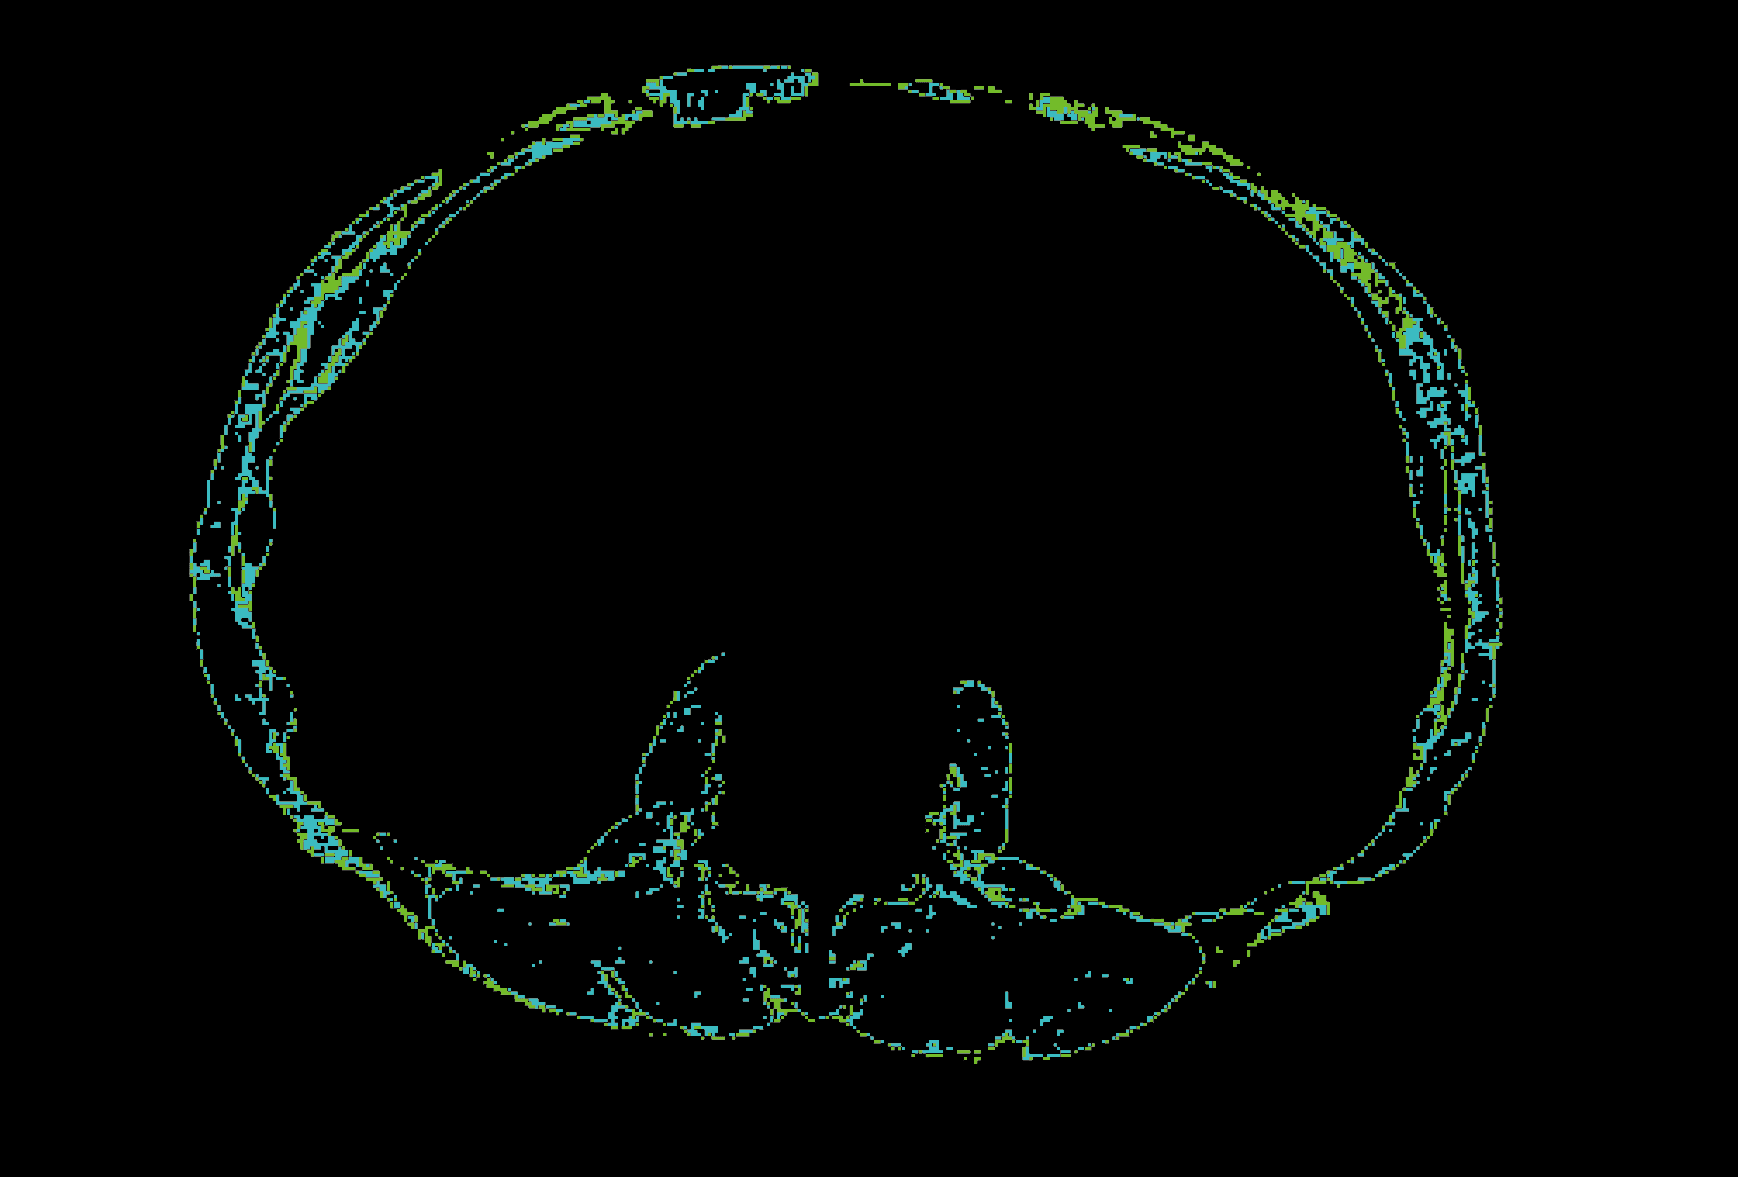

복부 CT 영상에서

L3 영상 자동 추출